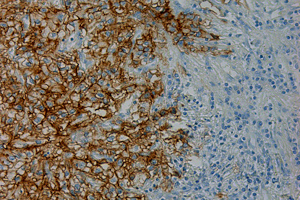

Hypoxia je fenomén, ktorému sa oddelenie venuje väčšinu svojho vedeckého života. Radosť je o to väčšia, že proteín CA IX (karbonická anhydráza IX) a jeho pH-regulačná funkcia, ktoré sú kľúčové pre hypoxickú adaptáciu nádorových buniek, boli objavené práve na Oddelení nádorovej biológie VÚ BMC SAV. Profesor Peter J. Ratcliffe, čerstvý „nobelista“, je spoluautorom článku o hypoxickej regulácii CA IX a s našimi kolegami, objaviteľmi CA IX, profesorom Jaromírom Pastorekom a profesorkou Silviou Pastorekovou, majú viaceré spoločné práce. Dôležitosť hypoxie spočíva v tom, že je charakteristická takmer pre všetky pevné nádory a zvyšuje metastatický potenciál nádorových buniek. Expresia CA IX je výrazne indukovaná v nádoroch s nedostatkom kyslíka a v celosvetovom meradle sa používa ako biomarker hypoxie. Pre väčšinu nádorov prítomnosť CA IX znamená zlú prognózu.